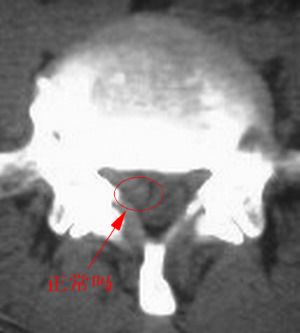

以下是引用fumaogui在2007-4-7 10:58:00的发言:[br]右侧腰4-5及骶1水平右侧神经根较对侧增粗,建议做mri排除一下神经源性肿瘤.

以下是引用zjzjr在2007-4-7 11:00:00的发言:[br]考虑腰4--5椎间盘突出长期压迫刺激致腰5神经根水肿,建议mr除外占位性病变。

以下是引用天南地北在2007-4-7 12:35:00的发言:[br]支持:考虑腰4--5椎间盘突出长期压迫刺激致腰5神经根水肿,建议mr除外占位性病变[br]神经根水肿可能性大